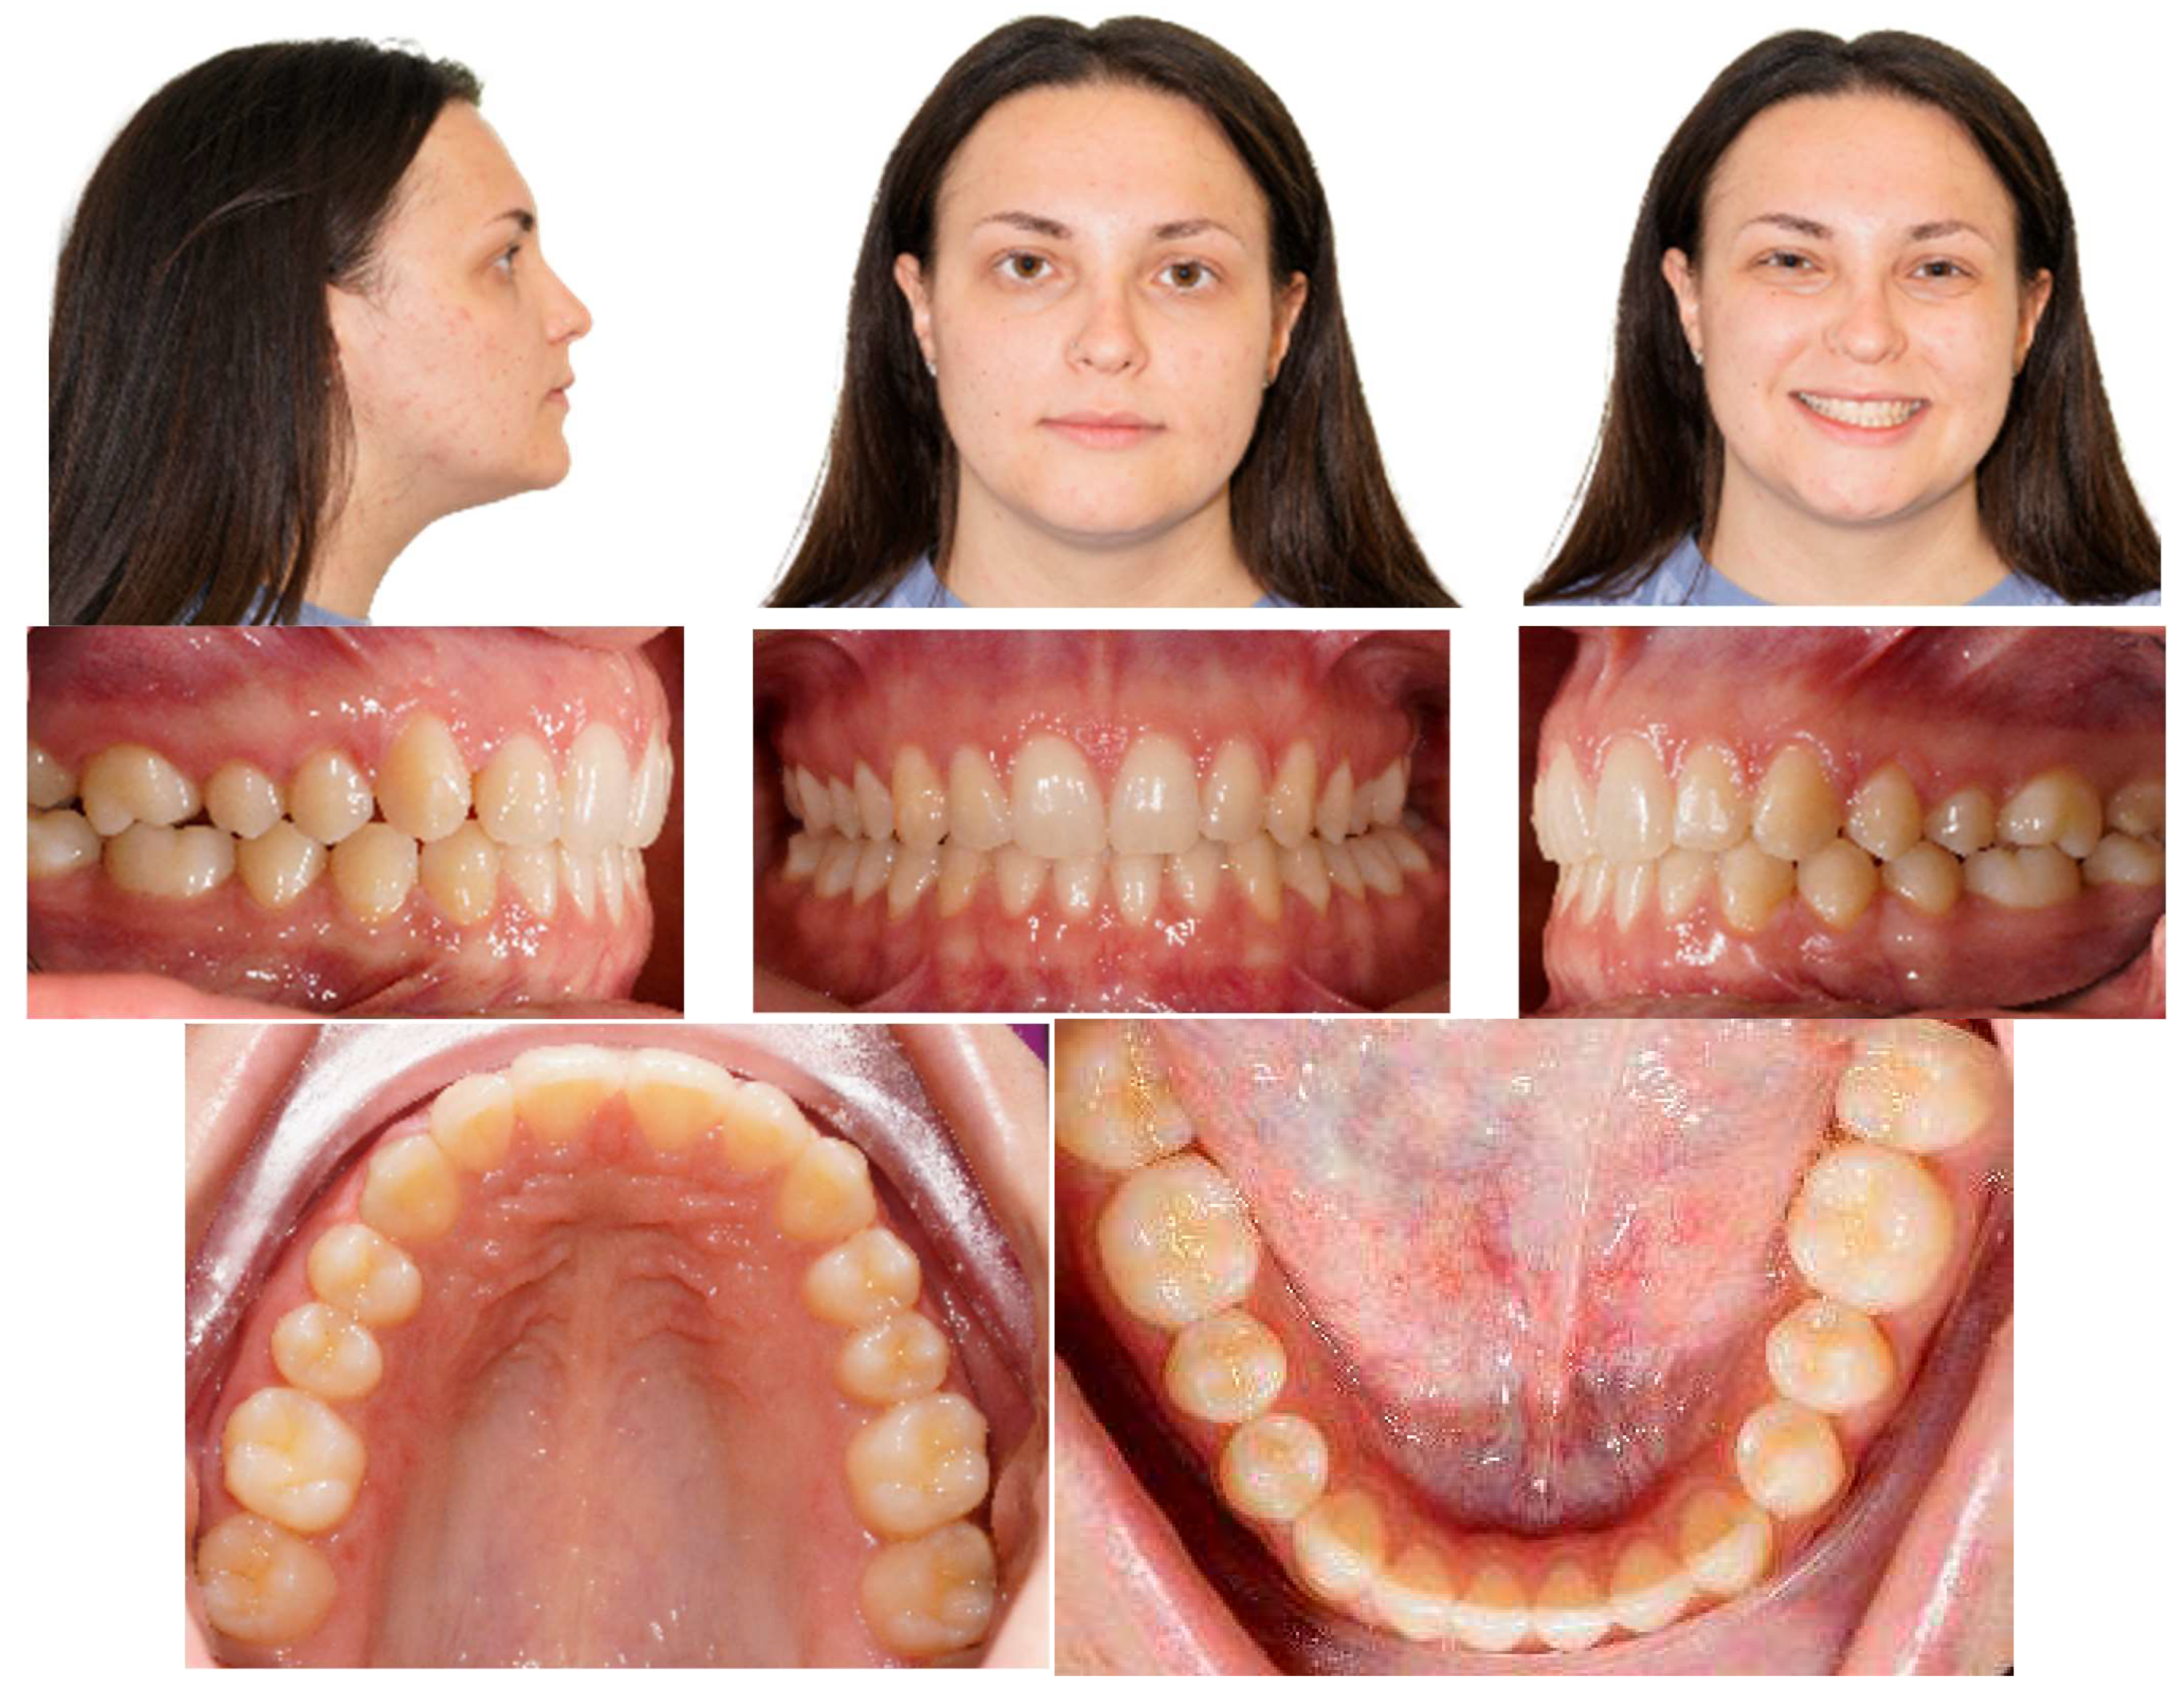

4.2. Results

Post-treatment records of the patient successfully treated using a combination of cantilever mechanics with TADs and clear aligners show a control of the facial aesthetics from the frontal and lateral perspectives with a harmonious soft-tissue profile. Final clinical records show good aesthetics and the functional recovery of the upper canines in the arch. A Class I canine relationship was achieved, and overbite and overjet were normalized. The correction of crowding was carried out (Figure 17).

Figure 17.

Post-treatment extraoral and intraoral pictures.

At the end of the treatment, cephalometric radiographs show the good control of the upper and lower inclination. The radiographic evaluation shows an ideal root parallelism and a preserved periodontal health in the canine region (Figure 18). Retention was achieved through Vivera in the upper arch and via a bonded lingual retainer in the lower arch. No TAD failures were observed.

Figure 18.

Final radiographs and landmarks.